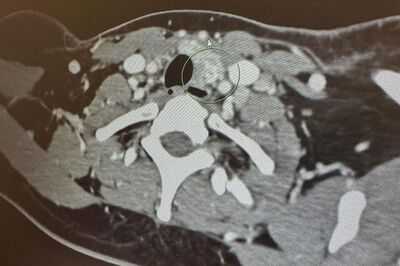

The terrified mum had a CT scan and biopsy, which confirmed the diagnosis of thyroid cancer, and she was booked in for a thyroidectomy - a procedure to remove all or part of the thyroid gland - and a left modified radical neck dissection - a procedure to remove cancerous lymph nodes - in April.